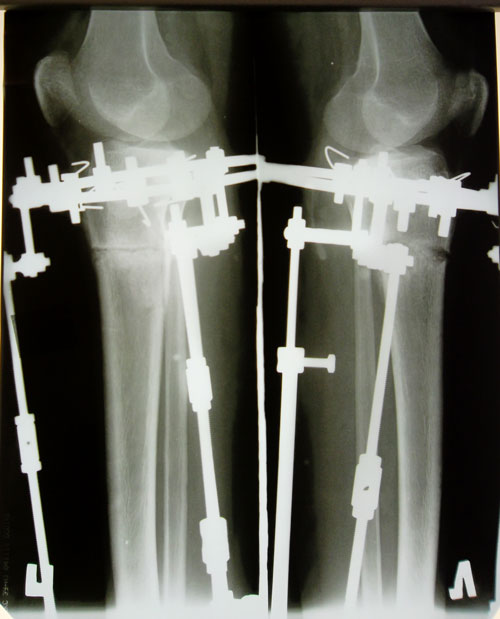

- Диагноз: О - образная кривызна ног

- Дата операции.: 07.02.2014

Исходник.

Дата операции 07.02.2014г.

Имеется более выраженная кривизна и ротация слева.